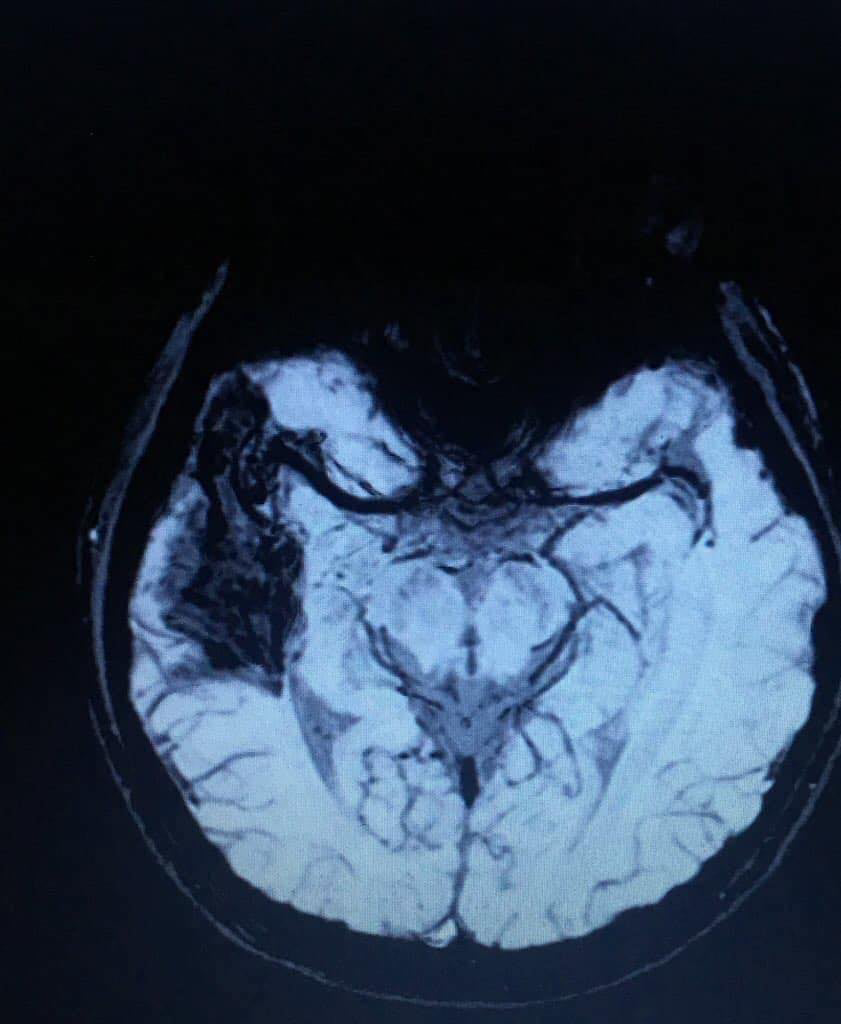

Kyle was diagnosed with Arteriovenous Malformation on the Right Temporoparietal Lobe last 2019. It developed into Epilepsy when 2020 came. He was also diagnosed with Panic Disorder in the same year. By 2021 he was diagnosed with Generalized Anxiety Disorder.